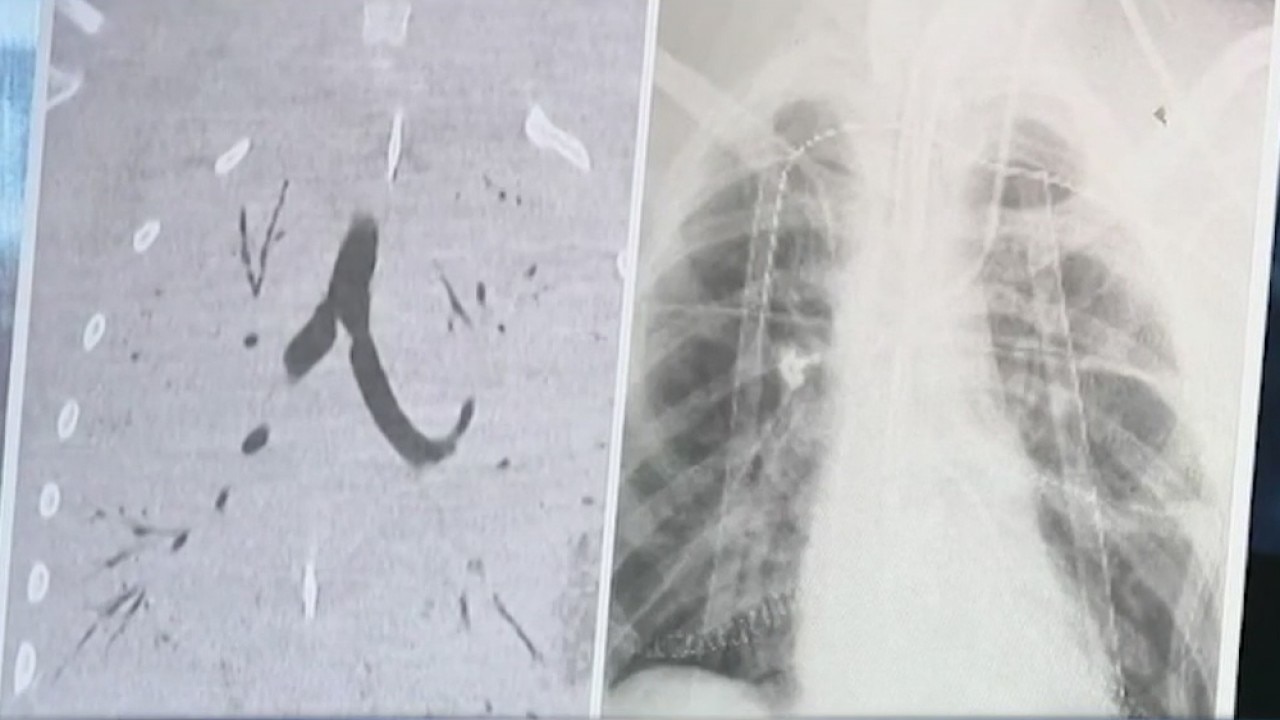

17-year-old undergoes double lung transplant, after lunge were damaged by vaping

Houston Methodist Transplant Center was the site of a recent double lung transplant on a 17-year0old whose lungs were damaged beyond healing due to vaping. Dr. Howard Huang explains to Melissa Wilson how vaping damages lungs.